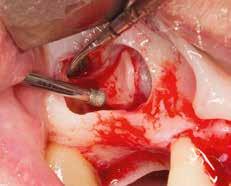

Im Zuge implantatprothetischer Rehabilitationen wird bei Vorlie gen einer reduzierten bukko-oralen Alveolarkammbreite bzw. auch der (in geringem Maße) -höhe eine vorangehen de knöcherne, latero-vertikale Augmen tation durchgeführt, um eine erfolgreiche ossäre Verankerung des Implantats wie auch ein ansprechendes ästhetisches Ergebnis nach abgeschlossener prothe tischer Versorgung anzustreben (siehe Abb. 1–8). Hierfür stehen verschiedene augmentative Operationstechniken zur Verfügung, wobei die autologe Blockaugmentation bislang am häufigsten angewandt wird. Obwohl autologe Knochenblöcke nach wie vor als „Gold standard“ gelten, kommen allogene, personalisierte, CAD/CAM-gefräste Knochenblöcke aufgrund ihrer hohen Passgenauigkeit vermehrt bei 3D-kom plexen Knochendefekten zum Einsatz. Gewonnen werden allogene Knochen blöcke vor allem aus Femurköpfen (nach sorgfältigster Spender:innen-Auswahl und Aufbereitung) von Patient:innen, welche eine Hüft-Endoprothese benö tigen. Diese Blöcke werden mithilfe des zuvor durchgeführten DVTs/CTs dem Defekt kongruent (3D-CAD) digital geplant und anschließend maschinell (3D-CAM) gefräst. Im Zuge des Eingriffs entfällt so der Vorgang der Blockentnah me, was wiederum zu einer deutlichen Verkürzung der OP-Dauer führt und in einer ausgeprägten Verminderung post operativer Beschwerden und möglicher Komplikationsquellen resultiert. Da der allogene Block dem Empfängerbett bereits (je nach Bildqualität) optimal angepasst ist, entfällt im Vergleich zur

Abb. 1: Intraoperative Ansicht des komplexen Defektes 21 nach Entfernung eines Wurzelspit zen-resezierten Zahnes nach Monaten

Abb. 3: Fixierung des kongruenten, allogenen Knochenblocks mit einer Osteosynthese schraube stabilisiert

autologen Blockaugmentation meist eine zeitintensive Adaptierung des Augmenta tes an das Empfängerbett. Postoperativ konnte im Rahmen lateraler Augmentationen mittels allogener Kno chenblocktransplantate allerdings eine deutlich höhere Rate an Wundheilungs störungen/Komplikationen – vor allem Schleimhautdehiszenzen – beobachtet

werden. Für ein komplikationsloses Einheilen des Knochenblocks ist eine suffiziente Wundheilung des umgeben den Weichgewebes notwendig.